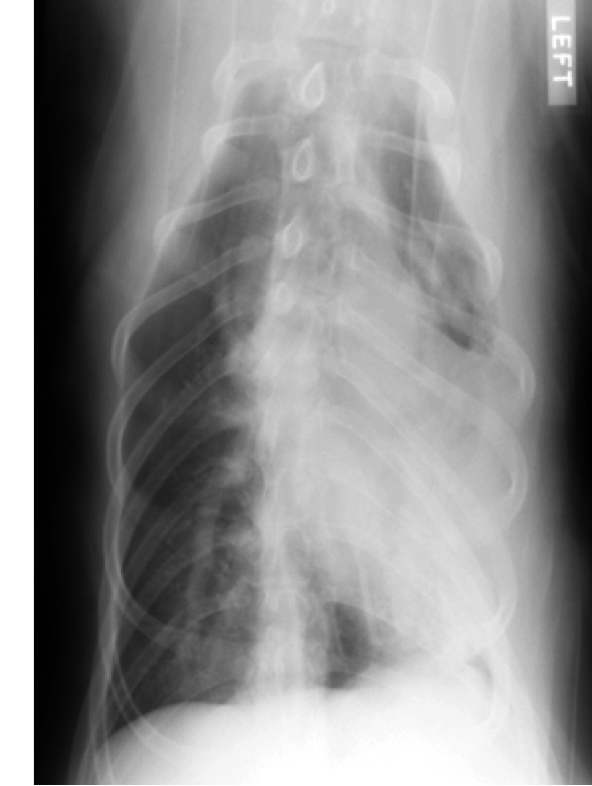

Q

classify the location/pattern and what is likely ddx

A

caudodorsal

Ddx: cardiogenic or non-cardiogenic pulmonary edema

Likely non-cardiogenic pulmonary edema because cardiac silhouette looks fine